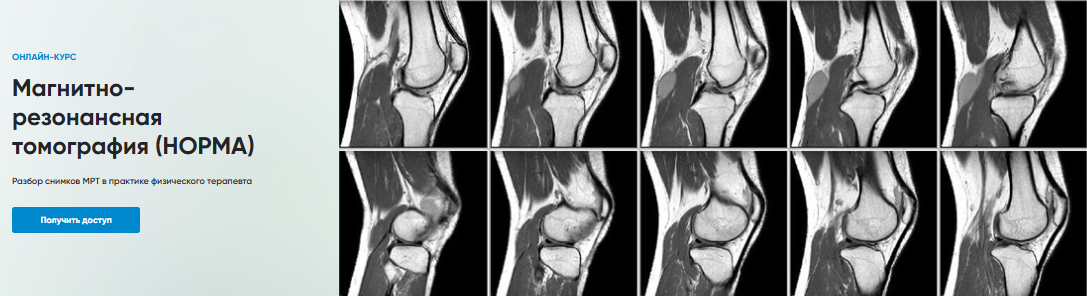

Магнитно-резонансная томография (НОРМА)

Разбор снимков МРТ в практике физического терапевта

1. МРТ Коленного сустава

2. МРТ Голеностопного сустава

3. МРТ Запястье

4. МРТ Локтевого сустава

5. МРТ Плечевого сустава

6. МРТ Поясничного отдела позвоночника

7. МРТ Тазобедренного сустава

8. МРТ Шейного отдела позвоночника